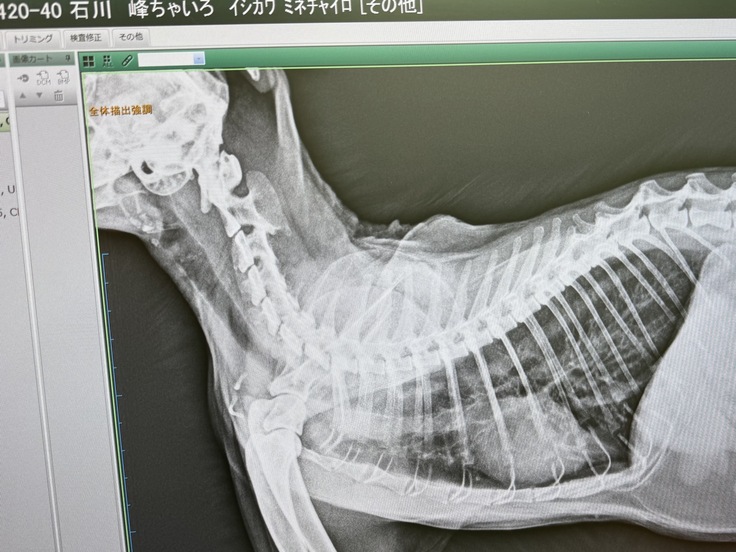

急いで当方のかかりつけ医に連れて行き、入院となりました。喘息に加えて気管支炎もあり、肺炎になり掛けていました。

翌日には呼吸状態は落ち着き安堵いたしましたが、喘息は想像以上に重く、強い薬は免疫力を下げてしまうため、改めて治療方針の提案をいただきました。